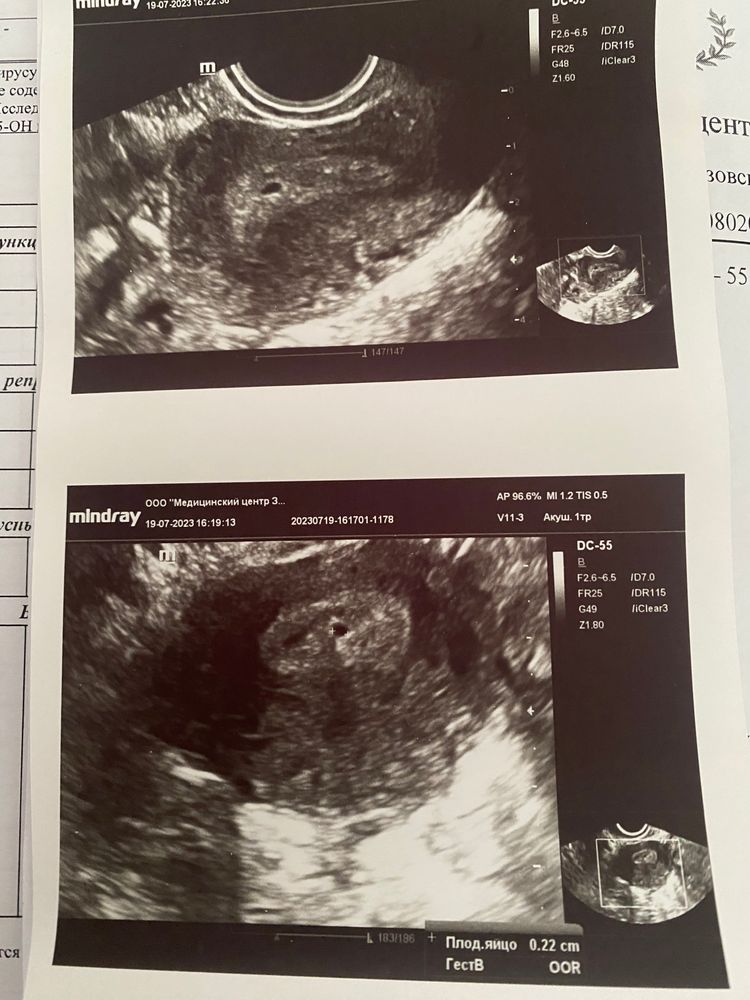

Результаты 4-го УЗИ ……

Кристина, 12 день

Кристина, овуляция по УЗИ 26 июня ….тогда же и ПА